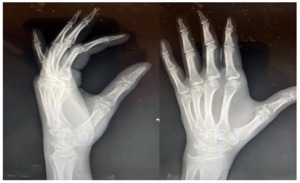

Repeat X rays showed good alignment and healing in progress (Fig.3) and physical therapy was started. The patient had gradual improvement in his wrist and thumb ROM with the help of physical therapy.

At his follow up 14 weeks post op, the patient was back to work, with pain rated at 2/10, described as intermittent that worsens with prolonged activity with slight stiffness on thumb extension. At 20 weeks post op the patient was asymptomatic and working without restrictions.